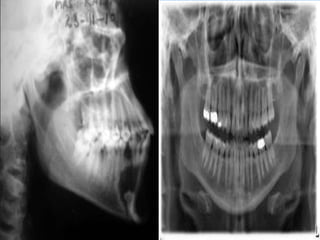

Radiographic examination

To evaluate condition of teeth , bone

Plain x-ray (a

Ex : panoramic , oblique lateral